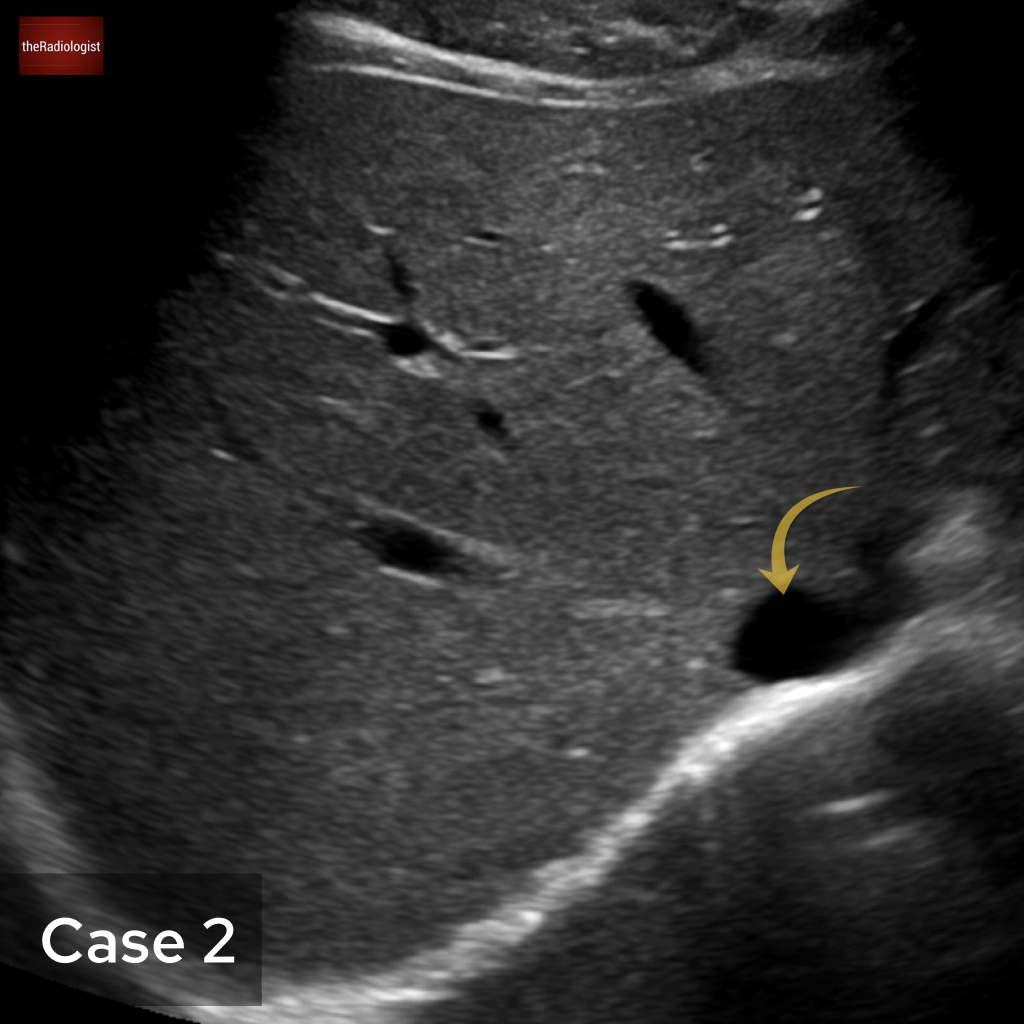

Case 2

Ultrasound this time. What is the arrow pointing at?

Choose one from the following options: